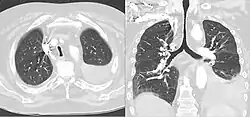

Saber-sheath trachea

A saber-sheath trachea also known as scabbard trachea is a trachea that has an abnormal shape. This manifests as a narrowing of the portion of the trachea located within the thorax, and a widening of the diameter of the posterior area of the trachea. The lateral measurement of tracheal diameter decreases. In saber-sheath trachea, the inner wall of the trachea is smooth, there are no nodules or areas of thickening.

On typical CT scans of the trachea, the normal appearance is oval, round, or horseshoe shaped. A saber-sheath trachea has distinct findings compared to normal tracheas on imaging, and may have additional features on CT besides intra-thoracic narrowing and widening diameter of the posterior portion. When cartilage becomes weak, as in saber-sheath trachea, CT scans can show the sides of the trachea curving inwards. This can be more apparent with forceful exhalation Moreover, the walls of the trachea within the thorax can also show slight thickening on CT. Another finding that can be seen is the hardening and becoming more bone-like of the cartilaginous rings in the trachea, a process called ossification.[5]